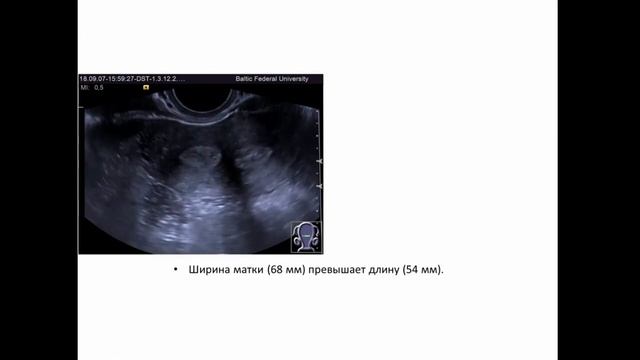

00:00 яичник в паховой грыже 00:12 гидрокольпос 00:31 апоплексия яичника 00:45 беременность раннего срока 00:57 синдром Шерешевского-Тёрнера 01:13 большая кистозная тератома имитирующая мочевой пузырь